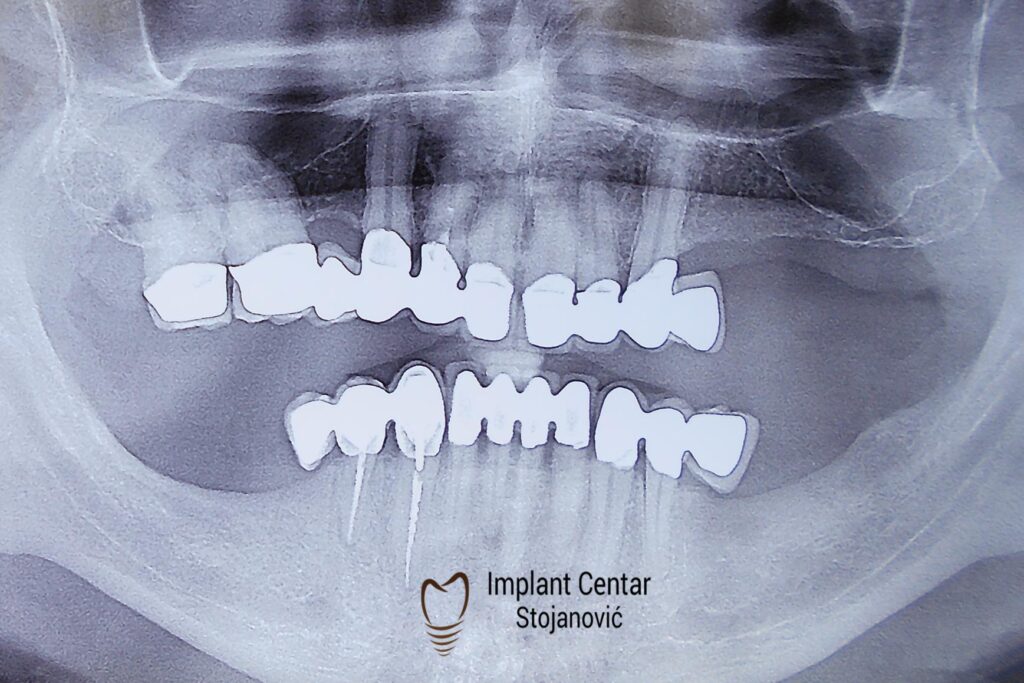

Na slici 1. slici 2. vidi se početno stanje — pacijent je imao prirodne zube, ali samo izradom novih mostova nije bilo moguće postići normalan odnos gornjih i donjih zuba (eugnatan zagrižaj).

Zbog toga je plan terapije uključivao vađenje svih preostalih zuba i ugradnju implantata u gornjoj i donjoj vilici. U gornjoj vilici postavljena su i dva tuberopterigoidna implantata, kao zamena za sinus lift proceduru, što se može videti na ortopan snimku nurađenom odmah nakon ugradnje (slika 3).